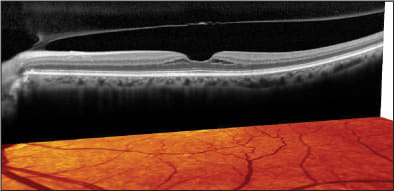

The patient assured me that he saw perfectly out of the left eye as recently as a year ago. I decided to attempt an OCT evaluation, which revealed a lamellar macular hole in the right eye and a severe vitreomacular traction syndrome in the left eye (Figures 7 and 8). The patient was referred for vitreo-retinal surgery in the left eye, which was performed successfully, and cataract surgery followed in both eyes, leading to 20/30 vision in the OD and 20/50 in the OS.

This is another case that demonstrates the ability of SD-OCT to see the things that can't be discovered on clinical exam alone. It also highlights the spectrum of vitreomacular interface abnormalities that are extremely common in clinical practice but rarely diagnosed prior to OCT.